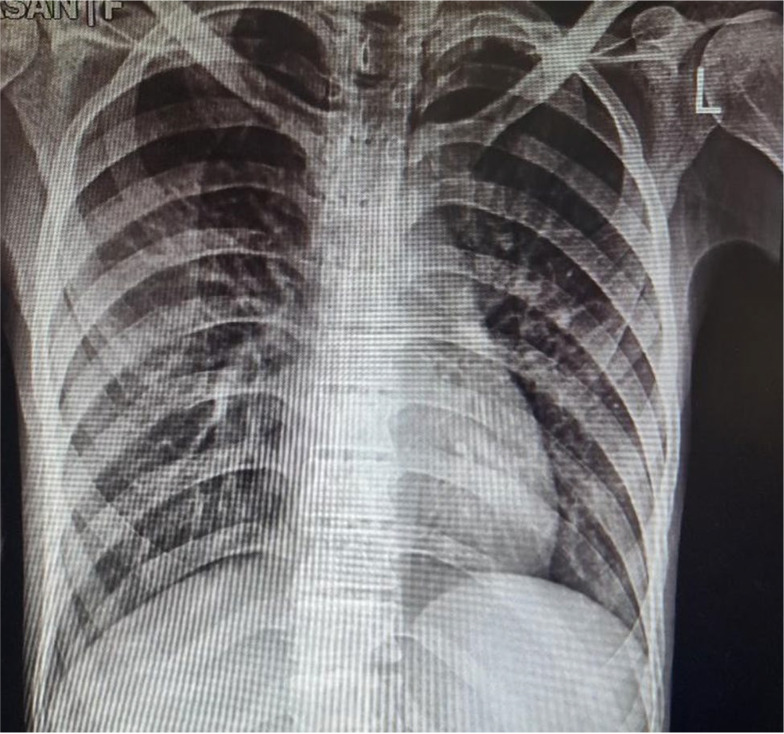

Progeria syndrome is a rare genetic disorder resulting in premature aging. General anesthesia is very challenging in these patients due to difficult intubation and age-related comorbidities. We describe spinal anesthesia management in a 30-year-old man with progeria syndrome. To our knowledge, this is the first report on using spinal anesthesia in this group of patients.